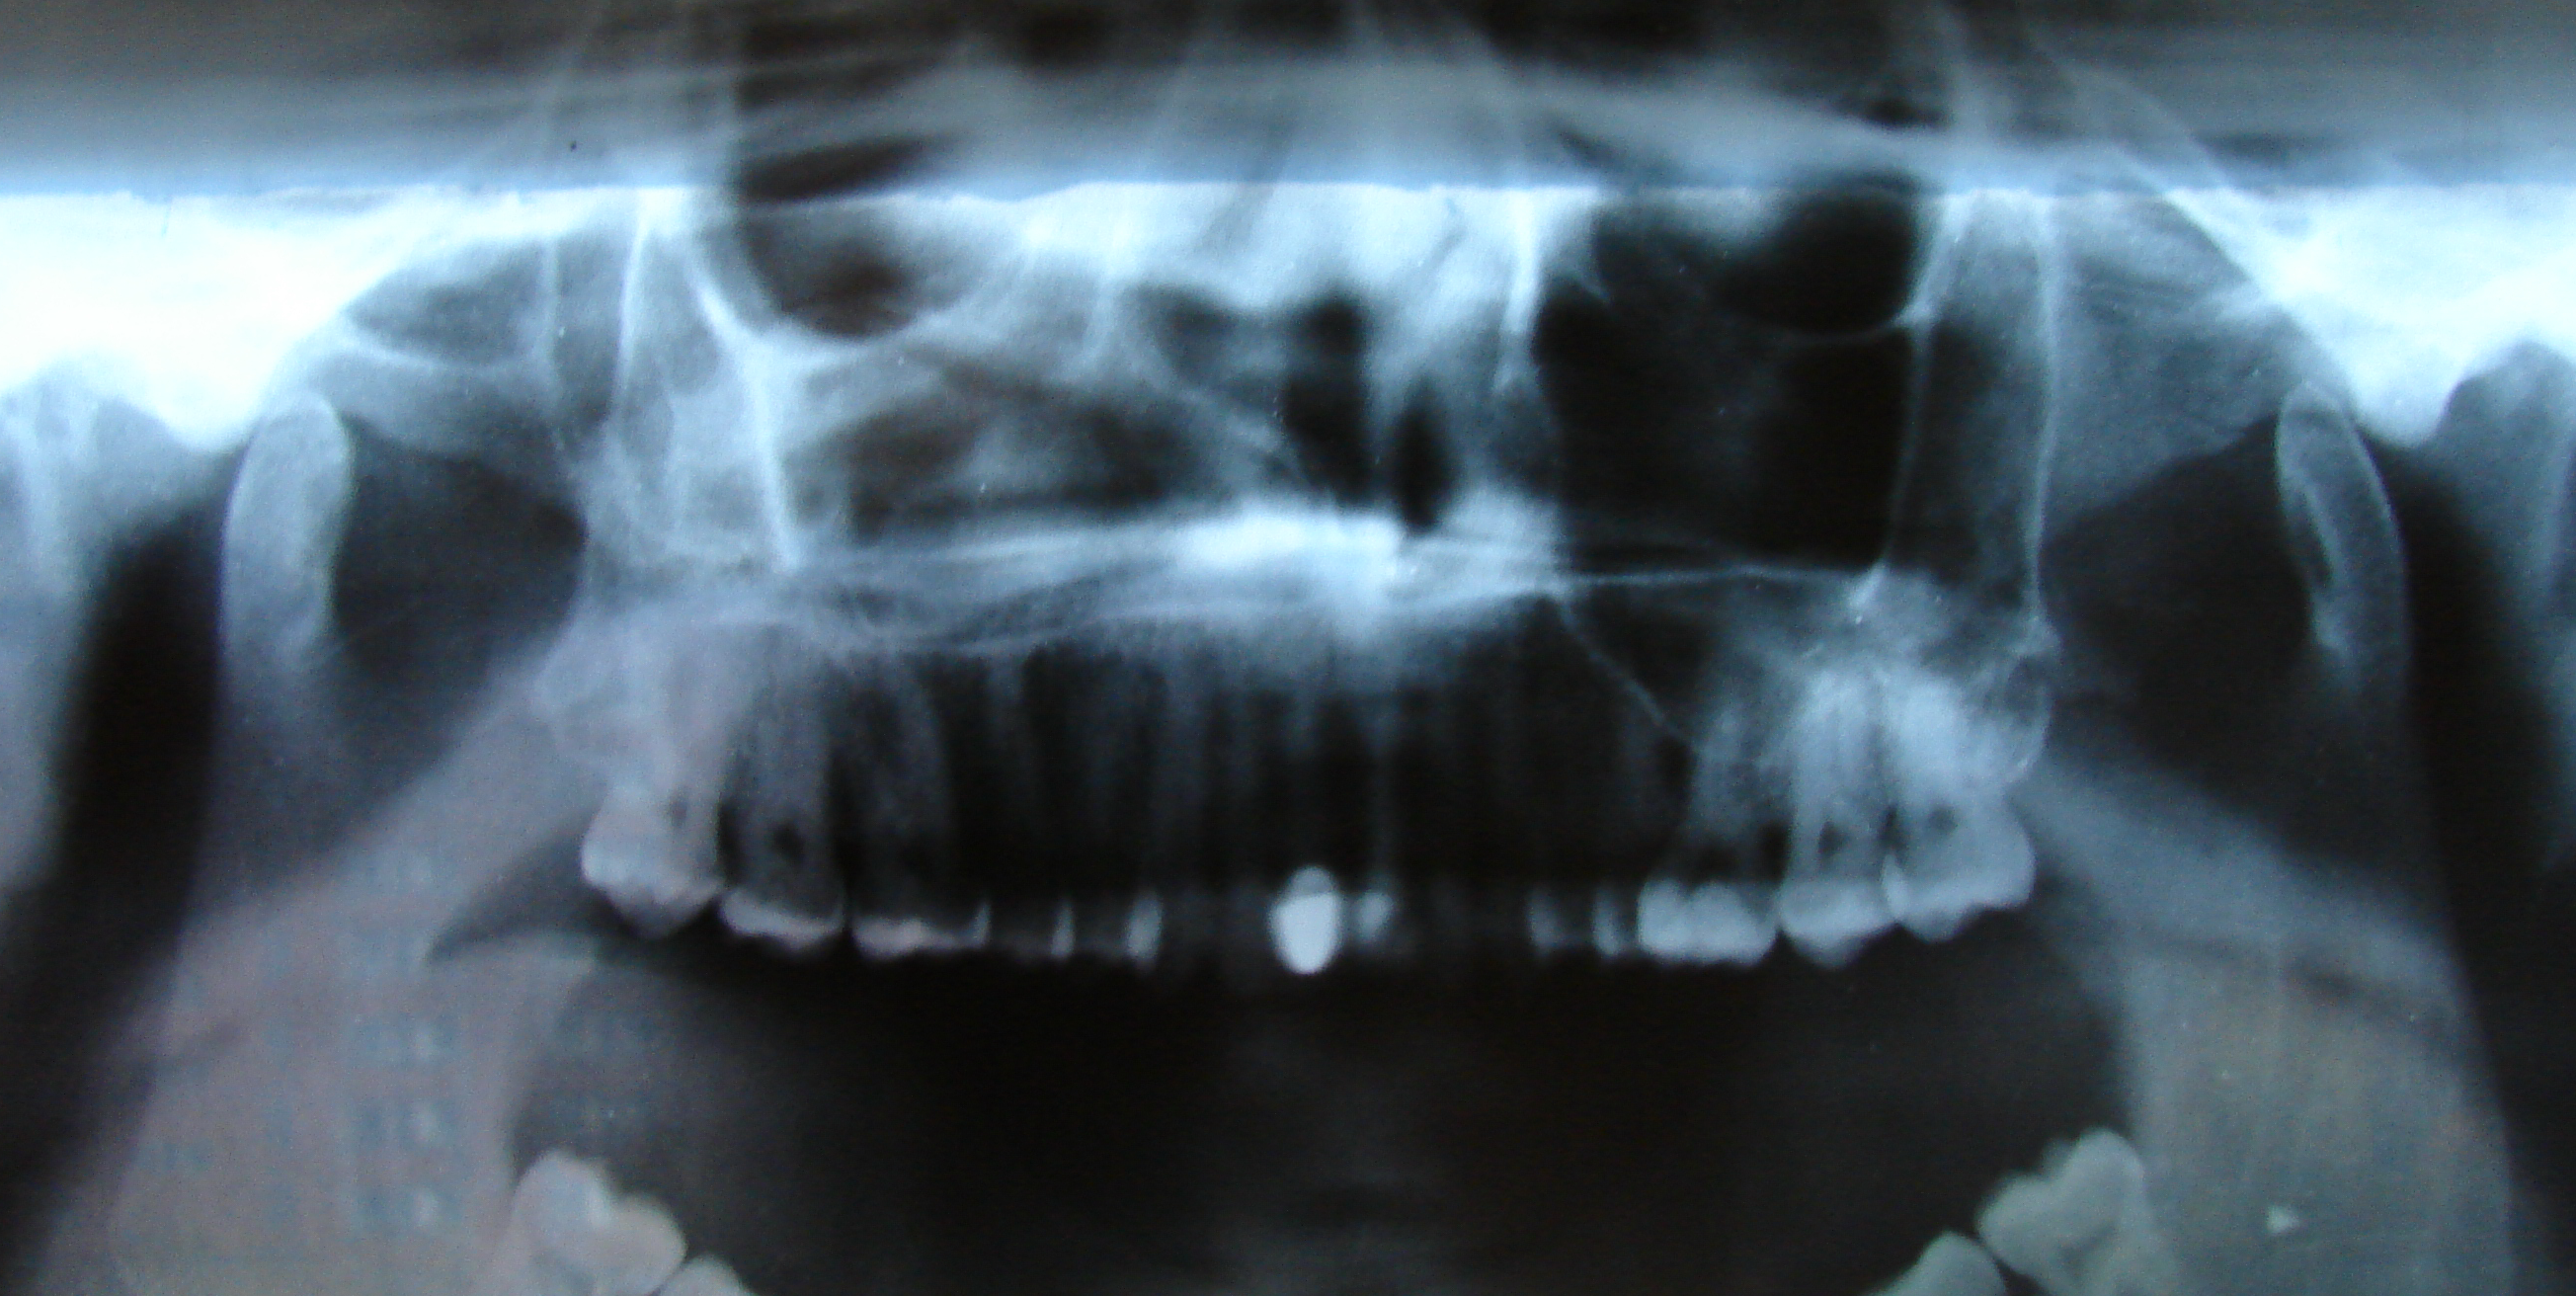

Рентгенография небного шва: Медицинские исследования и диагностика

Раздел: Фотопутеводитель